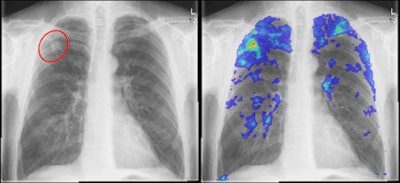

However, CAD might be able to help, serving as a prescreening, triage method for reducing the cost of TB screening algorithms. Since the software yields high sensitivity, it could be useful for performing triage of cases when used as a first reader. Cases found to be normal on CAD would be removed from the screening process, while abnormal studies would then be read by a human expert, Hogeweg said.

To test this hypothesis, the researchers sought to assess the performance of a research prototype CAD system (being jointly developed by the university's Diagnostic Image Analysis Group and Delft Imaging Systems) for detecting TB on chest radiographs in a high-risk screening setting. They also wanted to evaluate its potential as a triage tool.

It was trained using example of pixels in normal and abnormal regions, with moments of Gaussian derivatives extracted for each region. A classifier is then used to assign a score to each pixel, and each image receives one overall CAD score based on the 95% percentile of all of the pixel abnormality scores, Hogeweg said.